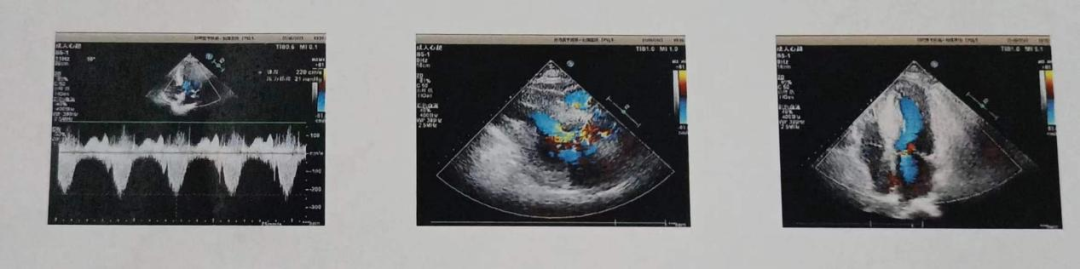

患者陈**,男,48岁,系“胸闷2年,加重1月”至蚌埠医学院第一附属医院心血管科就诊。静息状态下,室间隔明显增厚,最厚处为21mm,以基底段为甚,收缩期左室流出道前向血流加快,Vmax=4.52m/s,PG=82mmHg,SAM征阳性,二尖瓣大量反流。考虑HOCM。

患者术后恢复良好,并于术后七天顺利出院,胸闷症状得到显著改善。静息状态下,室间隔增厚,最厚处为18mm,收缩期左室流出道前向血流加快,Vmax=2.29m/s,PG=21mmHg,二尖瓣中量反流。

超声检查

术后即刻影像和左室流出道压力阶差

术后1周影像和左室流出道压力阶差